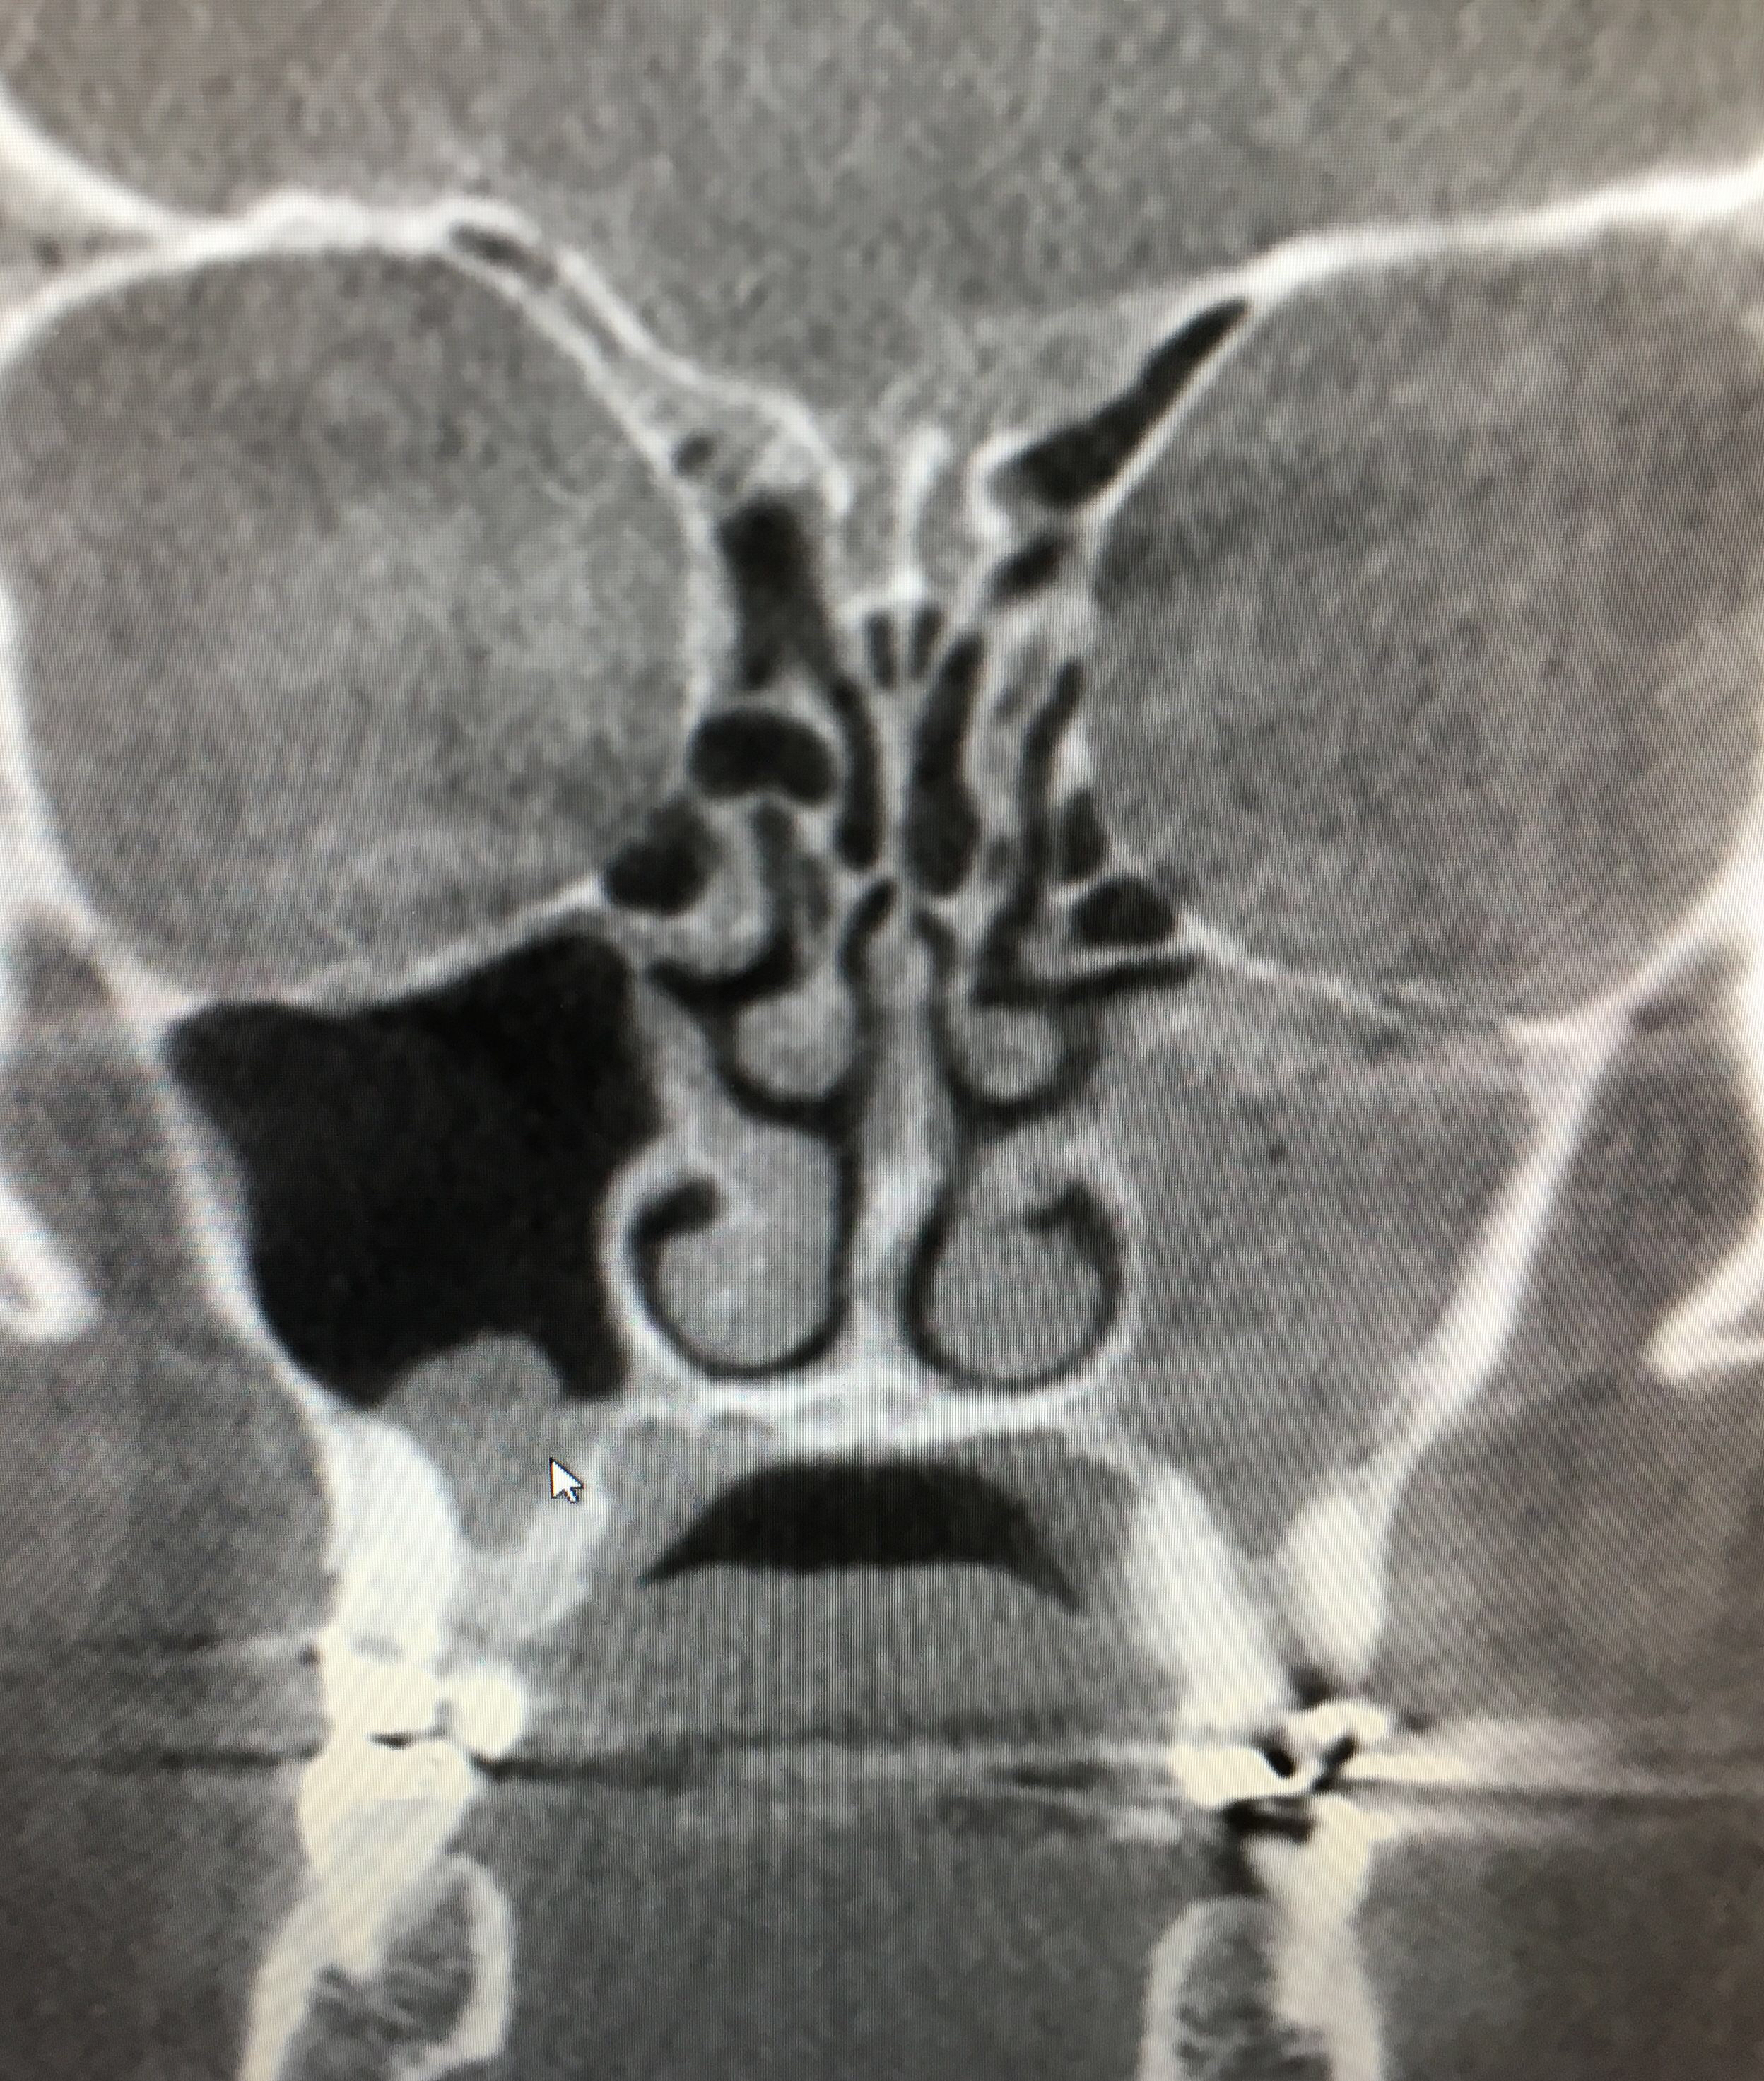

Cone beam CT is a much lower radiation 3D imaging technology that gives us a very clear picture of our sinuses as well as the cervical spine, temporomandibular joints, teeth, airway and bone.

These are two patients with identical symptoms, sinus and facial pressure that persisted and did not change with medication. Check out this video.

normal sinus versus filled left maxillary sinus

The take away from these two similar cases is that imaging was very helpful in establishing our diagnosis. One had no presence of sinus disease or infection but sinus pressure while the other had obvious signs of infection of multiple sinuses and was referred back to his ENT for a surgical consult. The underlying cause of the sinus pain without signs of sinus infection was determined to be the neck. Treatment to the neck resolved the patient’s symptoms.

If sinus pain is not responding to medical interventions and if the Cone Beam CT is negative check the neck. There are usually other signs present that the neck is not working optimally and the underlying cause.

How do you know you have a sinus infection? What if your pain and pressure continues even after antibiotics? A Cone Beam CT will show if you have a sinus infection or disease. If it shows that your sinuses are clear then your symptoms are being referred from your neck.